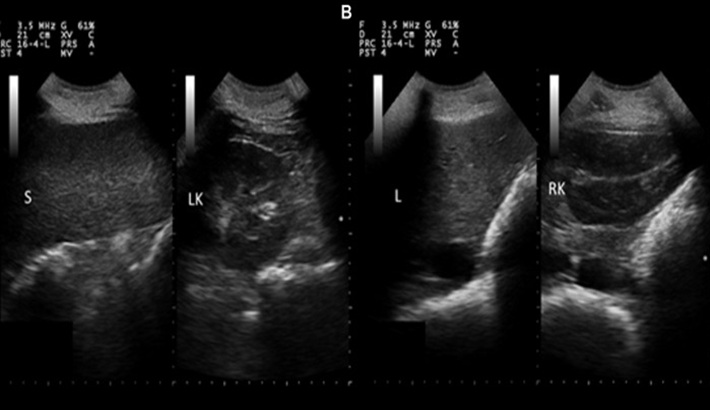

سونوگرافی کبد و طحال؛ چه اطلاعاتی در اختیار پزشک میگذارد؟

کبد و طحال از اندامهای حیاتی بدن هستند که نقش مهمی در تنظیم فرآیندهای متابولیک و سیستم ایمنی ایفا میکنند. بررسی دقیق این اندامها در بسیاری از بیماریها ضروری است؛ سونوگرافی کبد و طحال یکی از بهترین و بیخطرترین روشها برای ارزیابی وضعیت آنها محسوب میشود. این سونوگرافی به پزشک کمک میکند تا تغییرات بافتی، اندازه غیرطبیعی یا وجود ضایعات احتمالی را شناسایی کند.

سونوگرافی کبد چه اطلاعاتی میدهد؟

کبد بهعنوان بزرگترین غده بدن، وظایف حیاتی مانند سمزدایی، ذخیره انرژی و تولید پروتئینها را بر عهده دارد. تغییر در بافت یا اندازه این اندام میتواند نشانه بیماریهای جدی باشد.

سونوگرافی طحال چه کاربردی دارد؟

طحال نقش کلیدی در سیستم ایمنی و تولید سلولهای خونی دارد. هرگونه تغییر در اندازه یا بافت این اندام میتواند نشانه اختلالات خونی یا عفونی باشد.

تشخیص بزرگی طحال (اسپلنومگالی)

یکی از مهمترین مواردی که در سونوگرافی طحال بررسی میشود، افزایش غیرطبیعی اندازه آن است. این وضعیت ممکن است ناشی از بیماریهای عفونی، کبدی یا خونی باشد.

شناسایی کیستها و ضایعات طحال

سونوگرافی میتواند وجود کیستها یا تودههای غیرطبیعی در طحال را آشکار کند. شناسایی زودهنگام این مشکلات به درمان سریعتر کمک میکند.

بررسی آسیبهای ناشی از ضربه

در موارد تصادف یا آسیب شدید به شکم، سونوگرافی طحال میتواند پارگی یا خونریزی داخلی را مشخص کند.